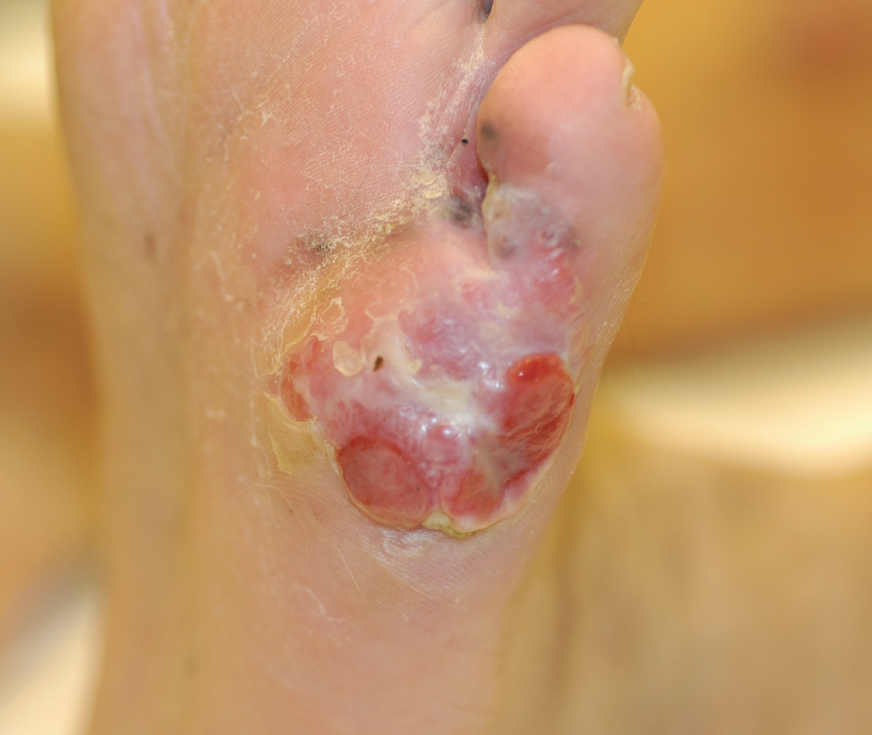

Melanoma

11/07/2013

Dustin Marks; Kristina Paley, MD

A 57-year-old white male with a history of diabetes and hypertension presents with a 3-month ulcer on his left, plantar foot.